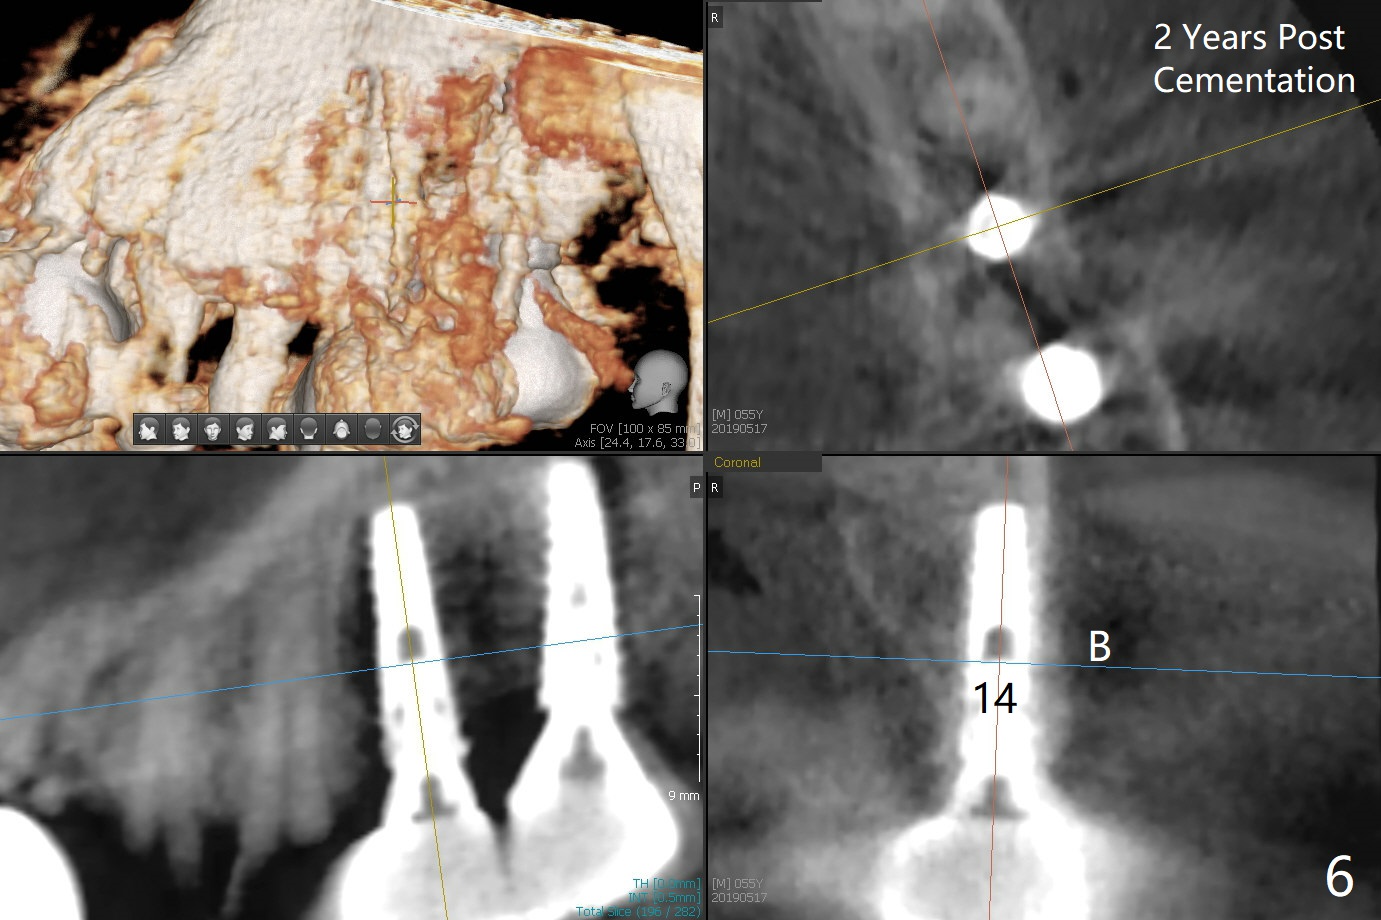

As shown by CT, the ridge at #14 is narrower than that of #15 (confirmed after incision), whereas the density at #14 is higher than that of #15. The osteotomies are established by combination of magic osteotomes and drills after change in trajectory (Fig.1-3). Following placement of 4.5x13 and 5x13 mm IBS implants and 6x4(3) and 6.5x4(3) mm pair abutments at #14 and 15 (Fig.4), flaps are sutured for hemostasis. Since the patient does not tolerate the surgery too well (unstable hypertension and oozing), immediate provisional is delayed. Periodontal dressing is applied instead. While the implants are healing, porcelain chips at the upper anterior bridge. There appears no bone resorption 6 months postop (Fig.5). Impression is taken following changing abutment to 5x4(2) mm at #14 and Diode gingivectomy. A panoramic film is taken 1 year 2 months post cementation. CT taken 2 years post cementation shows relatively good trajectory of these 2 implants (Fig.6,7).